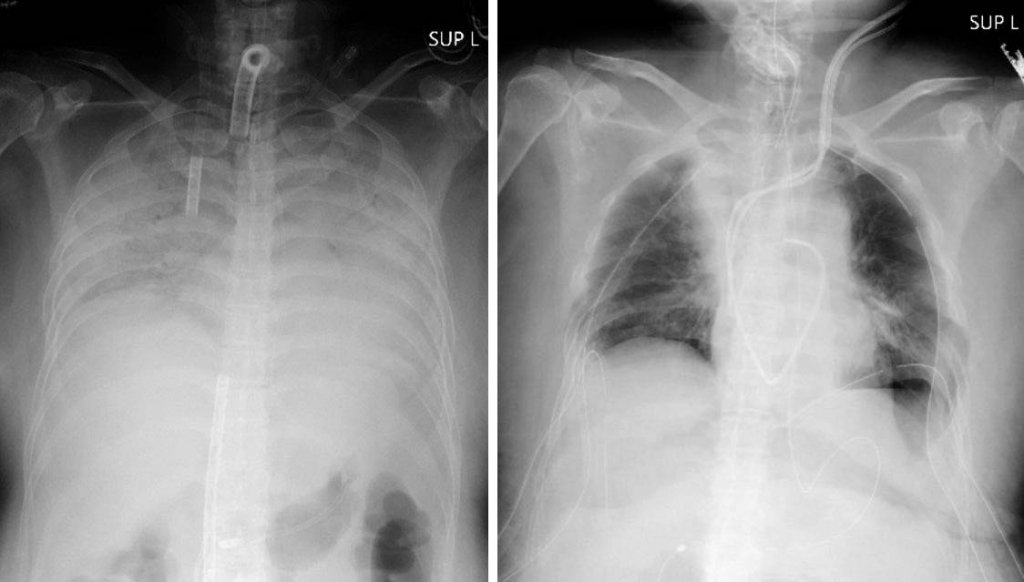

*Foto:Reprodução/Hospital Universitário de Kyoto

A paciente japonesa recebeu parte do tecido saudável do pulmão esquerdo do marido e do pulmão direito do filho para substituir os que haviam sido prejudicados pela infecção. Os três se recuperam bem. A mulher deve receber alta hospitalar dentro dos próximos dois meses.